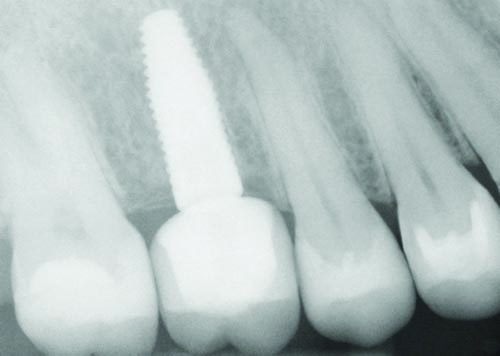

Fig. 13: A Straumann 4.8x14 implant was placed at the #3 site.

Tools

Fig. 14: A 4.1x14 Straumann implant was placed at the #13 site.

Fig. 15: A Straumann 4.8x12 implant was used at the #15 site.

Fig. 32

Figs. 30–32: Two weeks later, the fourth appointment was reserved for restoration try-in and final impressions on the endosteal implants. It was during the fifth appointment, scheduled for two weeks later, that the implant-supported IPS E.max crown restorations were delivered, as well as the other definitive maxillary restorations, and any necessary adjustments made. These postoperative radiographs confirmed healing at the #3, #12 and #15 sites, which were all ultimately restored with Straumann implants, custom titanium abutments and IPS E.max crowns.